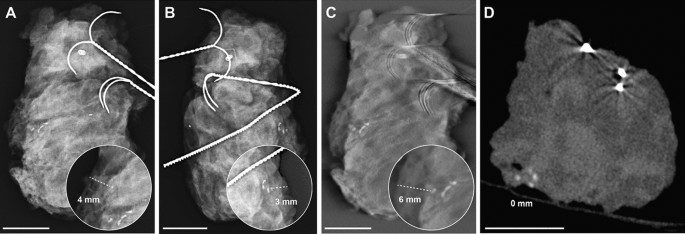

The mean measurement errors for the smallest distance of delineated microcalcifications to the resection margin for DM, DBT and CBCT (Table 2) were 10 mm, 14 mm and 6 mm (p = 0.002). There was a significant difference between CBCT and the other devices (CBCT vs. DM with p = 0.03 and CBCT vs. DBT with p = 0.006). No significant difference was observed between DM and DBT (p = 0.81). Imaging examples of two representative specimens are provided in Figs. 2 and 3. Both show clear differences in the projection of microcalcifications in relation to the resection margins between the three modalities.

Breast specimen with microcalcifications, histopathologically proven as invasive carcinoma of no special type, clip and wires in (A) and (B) the two standard projections of specimen mammography (DM), (C) in digital breast tomosynthesis (DBT) and (D) cone-beam computed tomography (CBCT) imaging. Whilst the microcalcifications project 4 or 3 mm from the margin in DM (dependent of projection), there are 6 mm distance from the margin in DBT as the smaller calcification was not reliably detected in the blinded measurements and in the CBCT the microcalcifications could be clearly localized directly at the margin due to real 3D placement and reconstructions. Some clear metal wear [middle of (A) and close to middle right margin in (B)] should not be mistaken for microcalcification. In addition, metal-related artifacts around the wires are seen in (C) DBT and (D) CBCT images. The white scalebar indicates 1 cm.